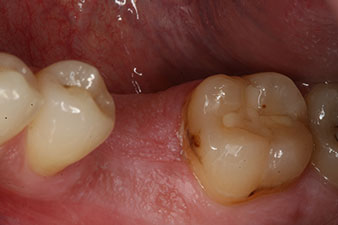

A first mandibular molar in a young patient had to be extracted due to extensive damage by caries with endodontic complications. Crowning the generally healthy neighbouring teeth could only be avoided with an implant. Six weeks after extraction, the alveolus proved to have insufficient bone. The implantation had to be combined with surrounding augmentation.

A 28-year-old patient with a history of heavy smoking had to have tooth 36 extracted as a result of recurring apical periodontitis.

Due to the generally intact neighbouring teeth the only way to fill the gap was an implant.

However, six weeks after the extraction incomplete ossification was found after preparation of the mucoperiosteal flap in the region of the former mesial alveolus.